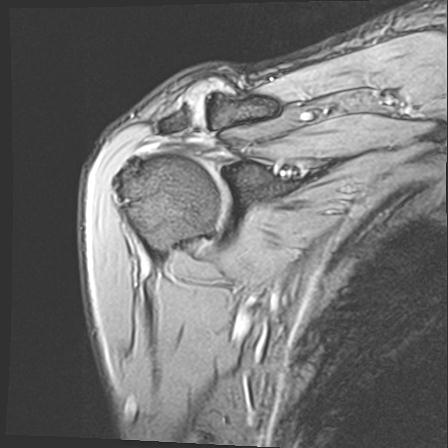

60058 3/9 11/4 右肩 2R+MRI 73歳男性 肩腱板損傷